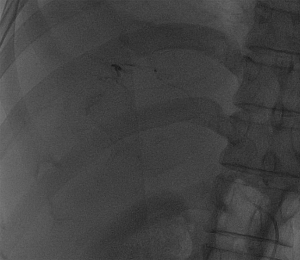

入院后,為患者給予補液,在局部麻醉下行DSA引導下經導管肝腫瘤動脈栓塞術。

肝癌破裂大出血并失血性休克患者往往病情急、危、重,如果治療不及時可能短期內死亡。未開展介入治療的醫院對此類患者只能給予輸血,補液,急診手術,在插管全麻下行開腹手術治療。但開腹手術往往切口長、手術時間長、手術創傷大,麻醉副作用大。可能術后出現肝功能衰竭,再出血,腹腔感染,切口疼痛,切口感染等并發癥。介入手術則往往較少出現這些并發癥。介入手術只需要在腹股溝穿刺一個2mm的小孔,置入導管到肝動脈,注入栓塞劑栓塞肝腫瘤的動脈,手術創傷小,止血可靠,除肝區疼痛及發熱外,較少出現其它并發癥,病人舒適度明顯提高,而且能早期進食及下地活動,恢復快,能縮短住院時間,具有療效好且微創的優點。